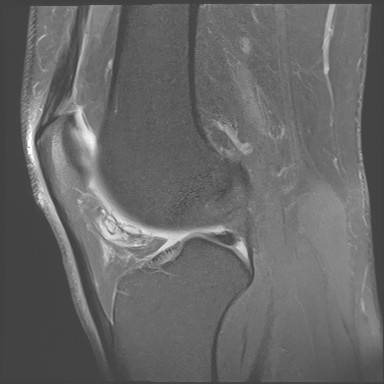

Figure 3 for case Orthovisc injections

Figure 3